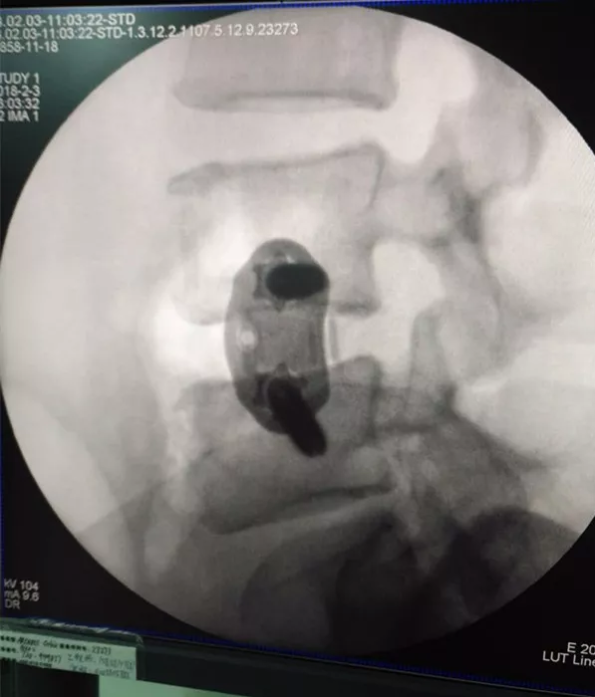

术后

XLIF手术采用单一小切口腹膜后入路完成椎管内间接减压、并进行可靠融合,无需后路内固定,为微创融合提供了又一条解决方案。该技术优势在于允许最大面积与高度的椎间融合器植入,无需剥离牵拉腹膜后大血管与神经,经腹膜后腰大肌肌纤维侧方入路,避免了对腹膜、大血管及神经的过度牵拉及剥离。更为关键的是,XLIF不必切除椎板、关节突关节等维持脊柱结构,避免术后腰背部僵硬疼痛等传统手术并发症。

该技术在我中心的顺利开展,是微创腰椎间融合技术的又一创新与发展,符合现代外科手术微创化的发展潮流。经研究证实,该术式手术创伤小、并发症少,避免了传统后入路内固定带来的二次创伤,在治疗适当的腰椎间盘突出症时,结合我们先进、娴熟的脊柱内镜减压技术、辅助显微镜甚至术中计算机导航,可以做到充分减压和牢固融合,获得满意的临床效果。